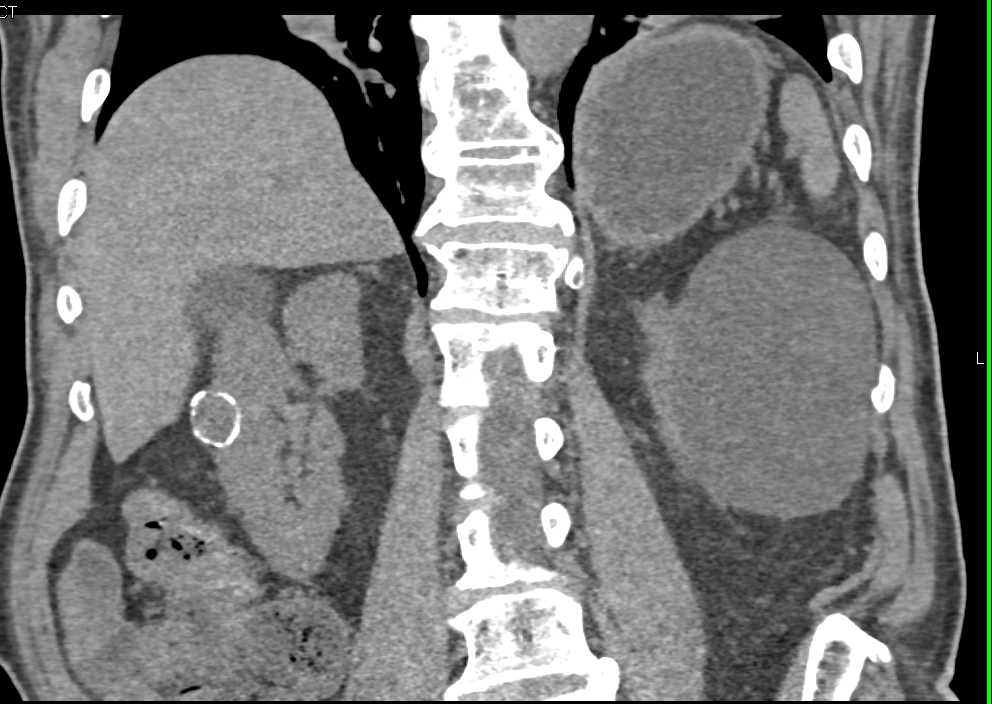

MEST or Mixed Epithelial Stromal Tumor